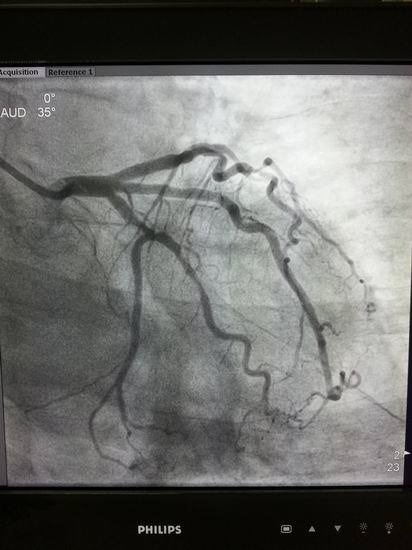

名称:高档数字减影、血管造影系统 Allura Xper FD20

主要功能:采用大平板科技,结合2K影像链,提供极佳图像细节解析能力,1250mA成像能力与“透心凉”高散热球管,“Refresh light”技术消除动态采集时的鬼影,图像质量更高。